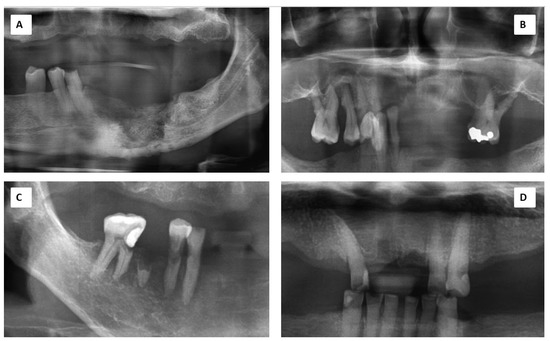

| Radiographic findings | Mixed osteolytic and sclerosis at the lower left mandible edentulous alveolar ridge. Cortical bone margin intact. | Bone surrounding teeth 14-16 and 26 were severely resorbed. Alveolar ridge margin appeared shaggy with multiple radiolucencies. | No abnormality detected on the maxilla and mandibular ridges. | Sequestrum-like radiopacity seen on left mandible with a focal region of tooth 34 appeared radiolucent. | Mixed osteolytic and sclerosis at the angle of mandible. Cortical bone margin still intact. Bone supporting around teeth 46-47 are sufficient. | Mixed osteolytic and sclerosis at the lower edentulous ridges. | Unknown | Lower edentulous ridge showed general horizontal resorption. |